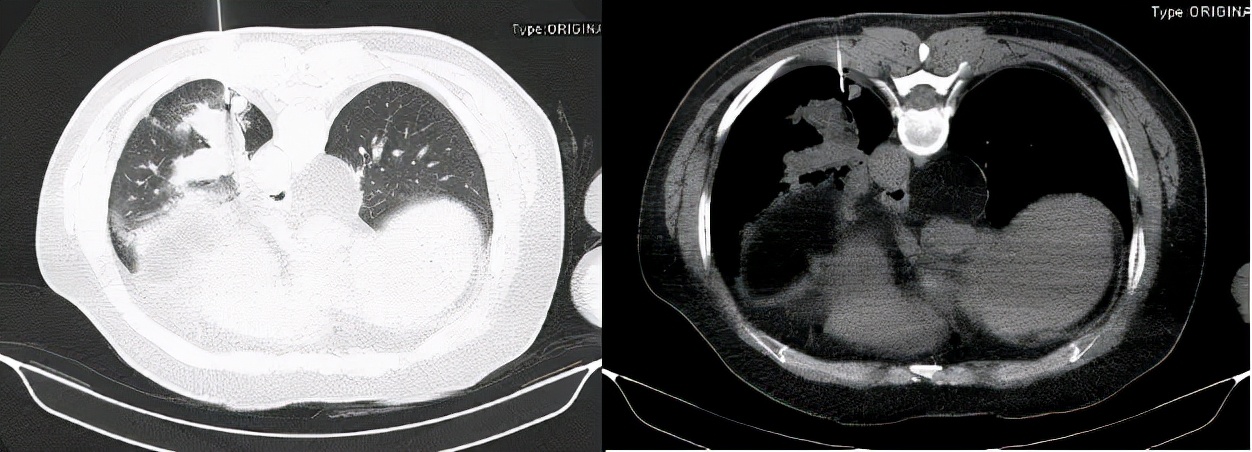

2020年4月28日胸部增强CT:1、左肺下叶后基底段见不规则团片影,较大层面约6.4×5.1cm,其内见少许点状钙化灶,增强后轻度强化,周围见斑片、条索影,邻近胸膜增厚、黏连。2、右肺中叶、左肺下叶、左侧斜裂小结节,较大者约0.4cm,多系炎性。3、双肺少许慢性炎症。4、心脏未见增大,肺动脉干稍增粗。5、左肺门淋巴结稍大。6、食管裂孔疝(图4及图5)。

图4:胸部增强CT(2020年4月28日)

图5:胸部增强CT纵隔窗(2020年4月28日)

2020年4月30日支气管镜检查:各级支气管粘膜光滑,通畅,未见异常(图6)。

图6:支气管镜下改变

BALF:送检TB-XPERT, GM试验,细菌和真菌培养均阴性。

2020年5月2日胸部CT:第二次经皮肺穿刺活检(图7),并抽出液化区血性液体(图8)。

图7:第二次经皮肺穿(2020-5-2)

图8:经皮肺穿刺抽出血性液体(2020-5-2)

病理诊断为:肺组织慢性炎,局灶纤维组织增生,慢性炎细胞聚集。穿刺液完善NGS及培养均查见曲霉菌。